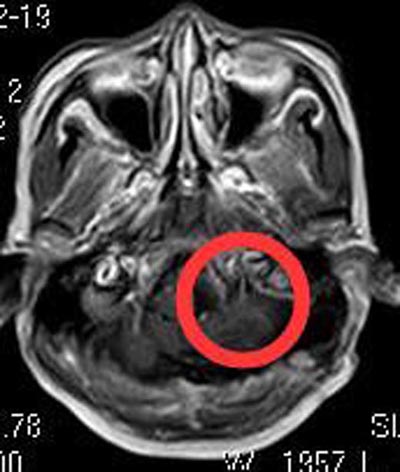

检查没有发现手术禁忌症,徐女士积极要求手术治疗。综合神经外科鲁明主任主刀,在全麻下行枕骨大孔区脑膜瘤切除术,术中显微镜下见肿瘤位于左侧桥延池区,黄白色,质中,后组颅神经受肿瘤压迫明显,椎动脉被肿瘤包绕,肿瘤基底部位于枕骨大孔区腹外侧硬膜;显微镜下全切肿瘤,后组颅神经、椎动脉保护完好,手术过程顺利。术后徐女士没有出现后组症状,左侧肢体麻木明显好转。病理结果:脑膜瘤,合体细胞型,WHO I级。

▲手术后